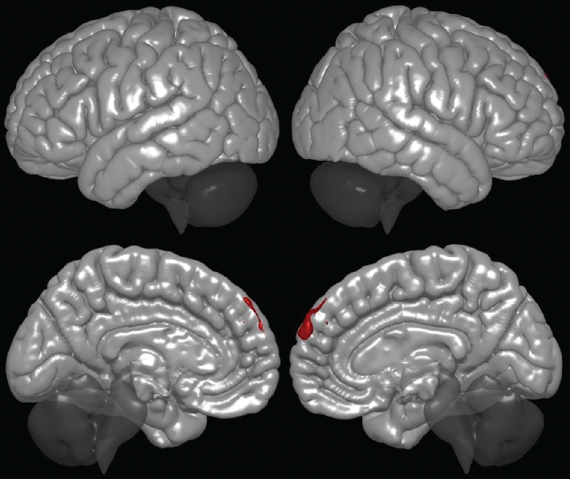

Оценка изменения функциональной коннективности при межгрупповом сравнении по отношению к данной сети показало увеличение кластеров в префронтальной области у пациентов группы № 1 (группы с удачным исходом трансплантации), что может свидетельствовать о восстановлении связей в данной нейросети за счет пула зеркальных/молчащих нейронов префронтальной области.

Увеличение функциональной коннективности верхних лобных извилин с обеих сторон (рис. 1), а также диффузно в области лобных долей, влечет изменения клинической картины: снижение выраженности уровня аффективных расстройств у пациентов, улучшение результата в тестах SDMT (тест символьно-цифрового кодирования).

Рис. 1. Кластер № 1 сети пассивного режима

Fig. 1. Cluster N 1 of the default mode network